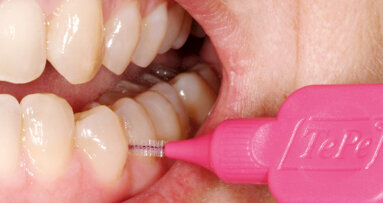

Ambulantní povaha zubních ordinací – která se vyznačuje pohybem velkého počtu pacientů a širokou škálou výkonů – vyžaduje spolehlivé, pečlivě dodržované hygienické postupy. Proto zde mají své místo standardní základní preventivní opatření:

Rukavice

Rukavice jsou nezbytnou součástí standardních opatření (obr. 2). Zubní lékaři by měli nosit lékařské rukavice vždy, když lze důvodně předpokládat, že by mohlo dojít ke kontaktu s krví nebo jinými potenciálně infekčními materiály, sliznicemi, porušenou kůží, potenciálně kontaminovanou kůží nebo kontaminovaným vybavením. Rukavice poskytují nejen bariérovou ochranu před mikroorganismy, ale také podstatně snižují objem přenesené krve a s tím spojených rizik křížové kontaminace při náhodném poranění jehlou nebo říznutí ostrými nástroji.